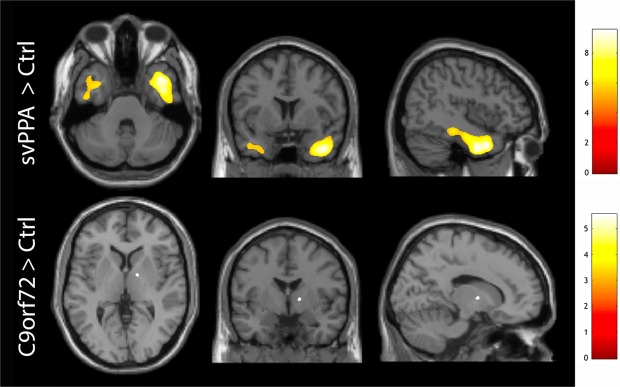

We further performed voxel-based analyses in the svPPA and C9orf72 groups compared to controls. In the svPPA > control contrast we could identify a large significant cluster (kE = 18886; pFWE-corr < 0.001) in the anterior right temporal lobe and a smaller cluster in the left temporal pole (kE = 2693; pFWE-corr < 0.001) after applying family-wise error (FWE) correction (Fig. 4, upper panel). In the C9orf72-mutation carriers > control contrast there was one small cluster located in the right posterior limb of the internal capsule (kE = 45; pFWE-corr = 0.03; Fig. 4, lower panel). No suprathreshold clusters were identified using the Control > svPPA or the Control > C9orf72 contrasts. Similar results were obtained if the svPPA patient with the highest SUVR values (case 1) was excluded from the analysis (data not shown).

Figure 4.

Voxel-based analysis of 18F-Flortaucipir retention. The upper panel shows significant voxels in the svPPA > Control contrast (p < 0.05) after correcting for family-wise errors (FWE). The lower panel shows C9orf72 > Control contrast at p < 0.05 FWE-corrected. Scales represent t-values. Please note that the orientation of the images follows neurological convention (left in the image represents patient left).